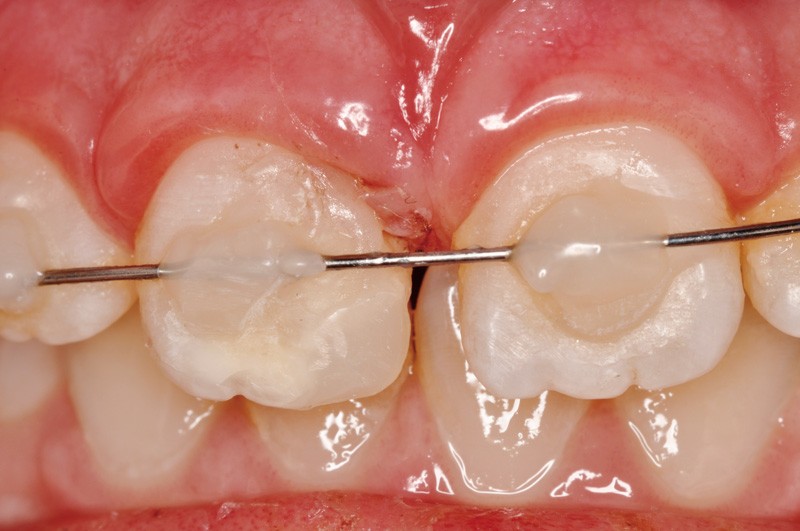

a à d Jeune patiente âgée de 8 ans, adressée suite à un traumatisme survenu 3 semaines auparavant, pour l’extraction de sa 21. La vue clinique montre un saignement ligamentaire, une mobilité coronaire et une fracture coronaire amélodentinaire longitudinale partant de l’angle mésial et se poursuivant en direction radiculaire sous-gingivale (a). Un test de vitalité positif indique que la dent est vitale, la radiographie permet de poser le diagnostic de fracture coronoradiculaire, et d’objectiver l’immaturité radiculaire (stade 8 de Nolla) (b). Une contention est mise en place et la plaie dentinaire coronaire est scellée au mieux par collage afin de limiter le risque d’une complication infectieuse (c). A 15 jours la dent est vivante et aucune complication n’est apparue (d). La patiente est revue après 3 mois pour déposer la contention, le test de vitalité est positif, et la radiographie de contrôle montre une apexogenèse en cours (e). Cependant la gencive s’est invaginée dans le trait de fracture (f). La zone est débridée sous microscope (g) puis scellée et reconstituée à l’aide d’un adhésif SAM et d’un composite fluide (h). Le contrôle radiographique à 6 mois est satisfaisant (i). Ce cas clinique illustre le fort potentiel des pulpes jeunes et du ligament alvéolodentaire à résister aux agressions et à assurer les fonctions dentinogénétiques et l’édification radiculaire.